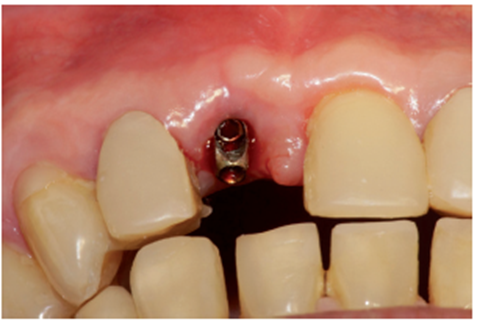

Após quatro meses foi realizado o segundo tempo cirúrgico com fresa cilíndrica diamantada, acessando somente o Cover Screw (Figura 22). O Cover Screw foi removido com a chave de 1.2 (Figura 23), um cicatrizador foi instalado (Figura 24) e o provisório foi reposicionado.

Na consulta seguinte, o cicatrizador foi removido e através do Kit de seleção de componentes, o pilar protético foi selecionado. O pilar de escolha foi o Ideale 3.3 x 4.0 x 1.5 angulado de 30 graus. Neste momento foi realizada uma moldagem com transferente de moldeira fechada (Figuras 25 e 26) para copiar o posicionamento tridimensional do implante e o modelo de trabalho foi obtido.

No laboratório, o técnico de prótese posicionou o pilar Ideale angulado no modelo (Figura 27) e confeccionou um incisivo central parafusado sobre ele, utilizando a coifa de provisório que o sistema oferece (Figura 28). Uma vez obtido o provisório, o cicatrizador voltou a ser removido e o pilar Ideale e o provisório foram instalados em boca (Figuras 30 e 31). O pilar foi torqueado em 20 Ncm e o parafuso da coroa foi torqueado em 10 Ncm. Após 15 dias, o provisório foi removido e observou-se o perfeito perfil de emergência que havia sido obtido (Figura 33). Neste novo momento foi posicionado sobre o pilar um transferente plástico de moldeira fechada do pilar Ideale, sendo que tanto o pilar como o dente 12 foram moldados (Figura 34) para a confecção de copings e posterior a aplicação da cerâmica (Figura 35).